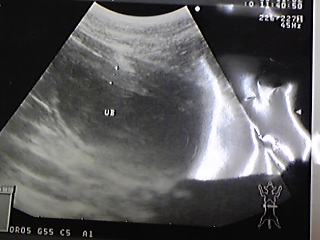

② 11月2日

やはり真ん中の黒い部分がオシッコ

その周りがギザギザしてる事から

炎症が良く分りますそして

ストラバイト結石が右上に 『こんにつゎ

』